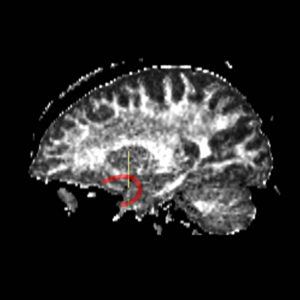

Cingulum BundleROI 1) on the superior side of the corpus, flush with the most anterior part of the corpus (based on sag view, but drawn on coronal view) ROI 2) on the first coronal slice where the L & R corpus connect, on the superior side of the corpus. ROI 3) on the first coronal slice where the L & R corpus connect, on the inferior side of the corpus. ROI 4) on the first coronal slice where the middle cerebellar peduncle is present.

FornixROI 1) on Coronal view, the first slice where the middle cerebellar peduncles are present ROI 2) posterior to ROI 1; large blobs drawn on coronal view where the middle cerebellar peduncle is clearly connected at bottom of slice

IC - Internal CapsuleROI 1) find anterior commisure on axial view and draw ROI on coronal slice on each side on midsag line Top boundary for ROI 1: Caudate/putamen line Bottom boundary for ROI 1: draw entire plane of AC; IC is only superior to AC line. ROI 2) go to the anterior most point of the corpus collosum according to saggital view. Draw ROI so it covers entire (left or right) hemisphere of brain on the perpendicular Coronal Slice.

unc - Uncinate FasciculusFind the most prominant (central) slice of the fornix according to saggital view. Go one slice anterior to the most anterior point of the fornix and draw Left and Right ROI 1 and ROI 2.